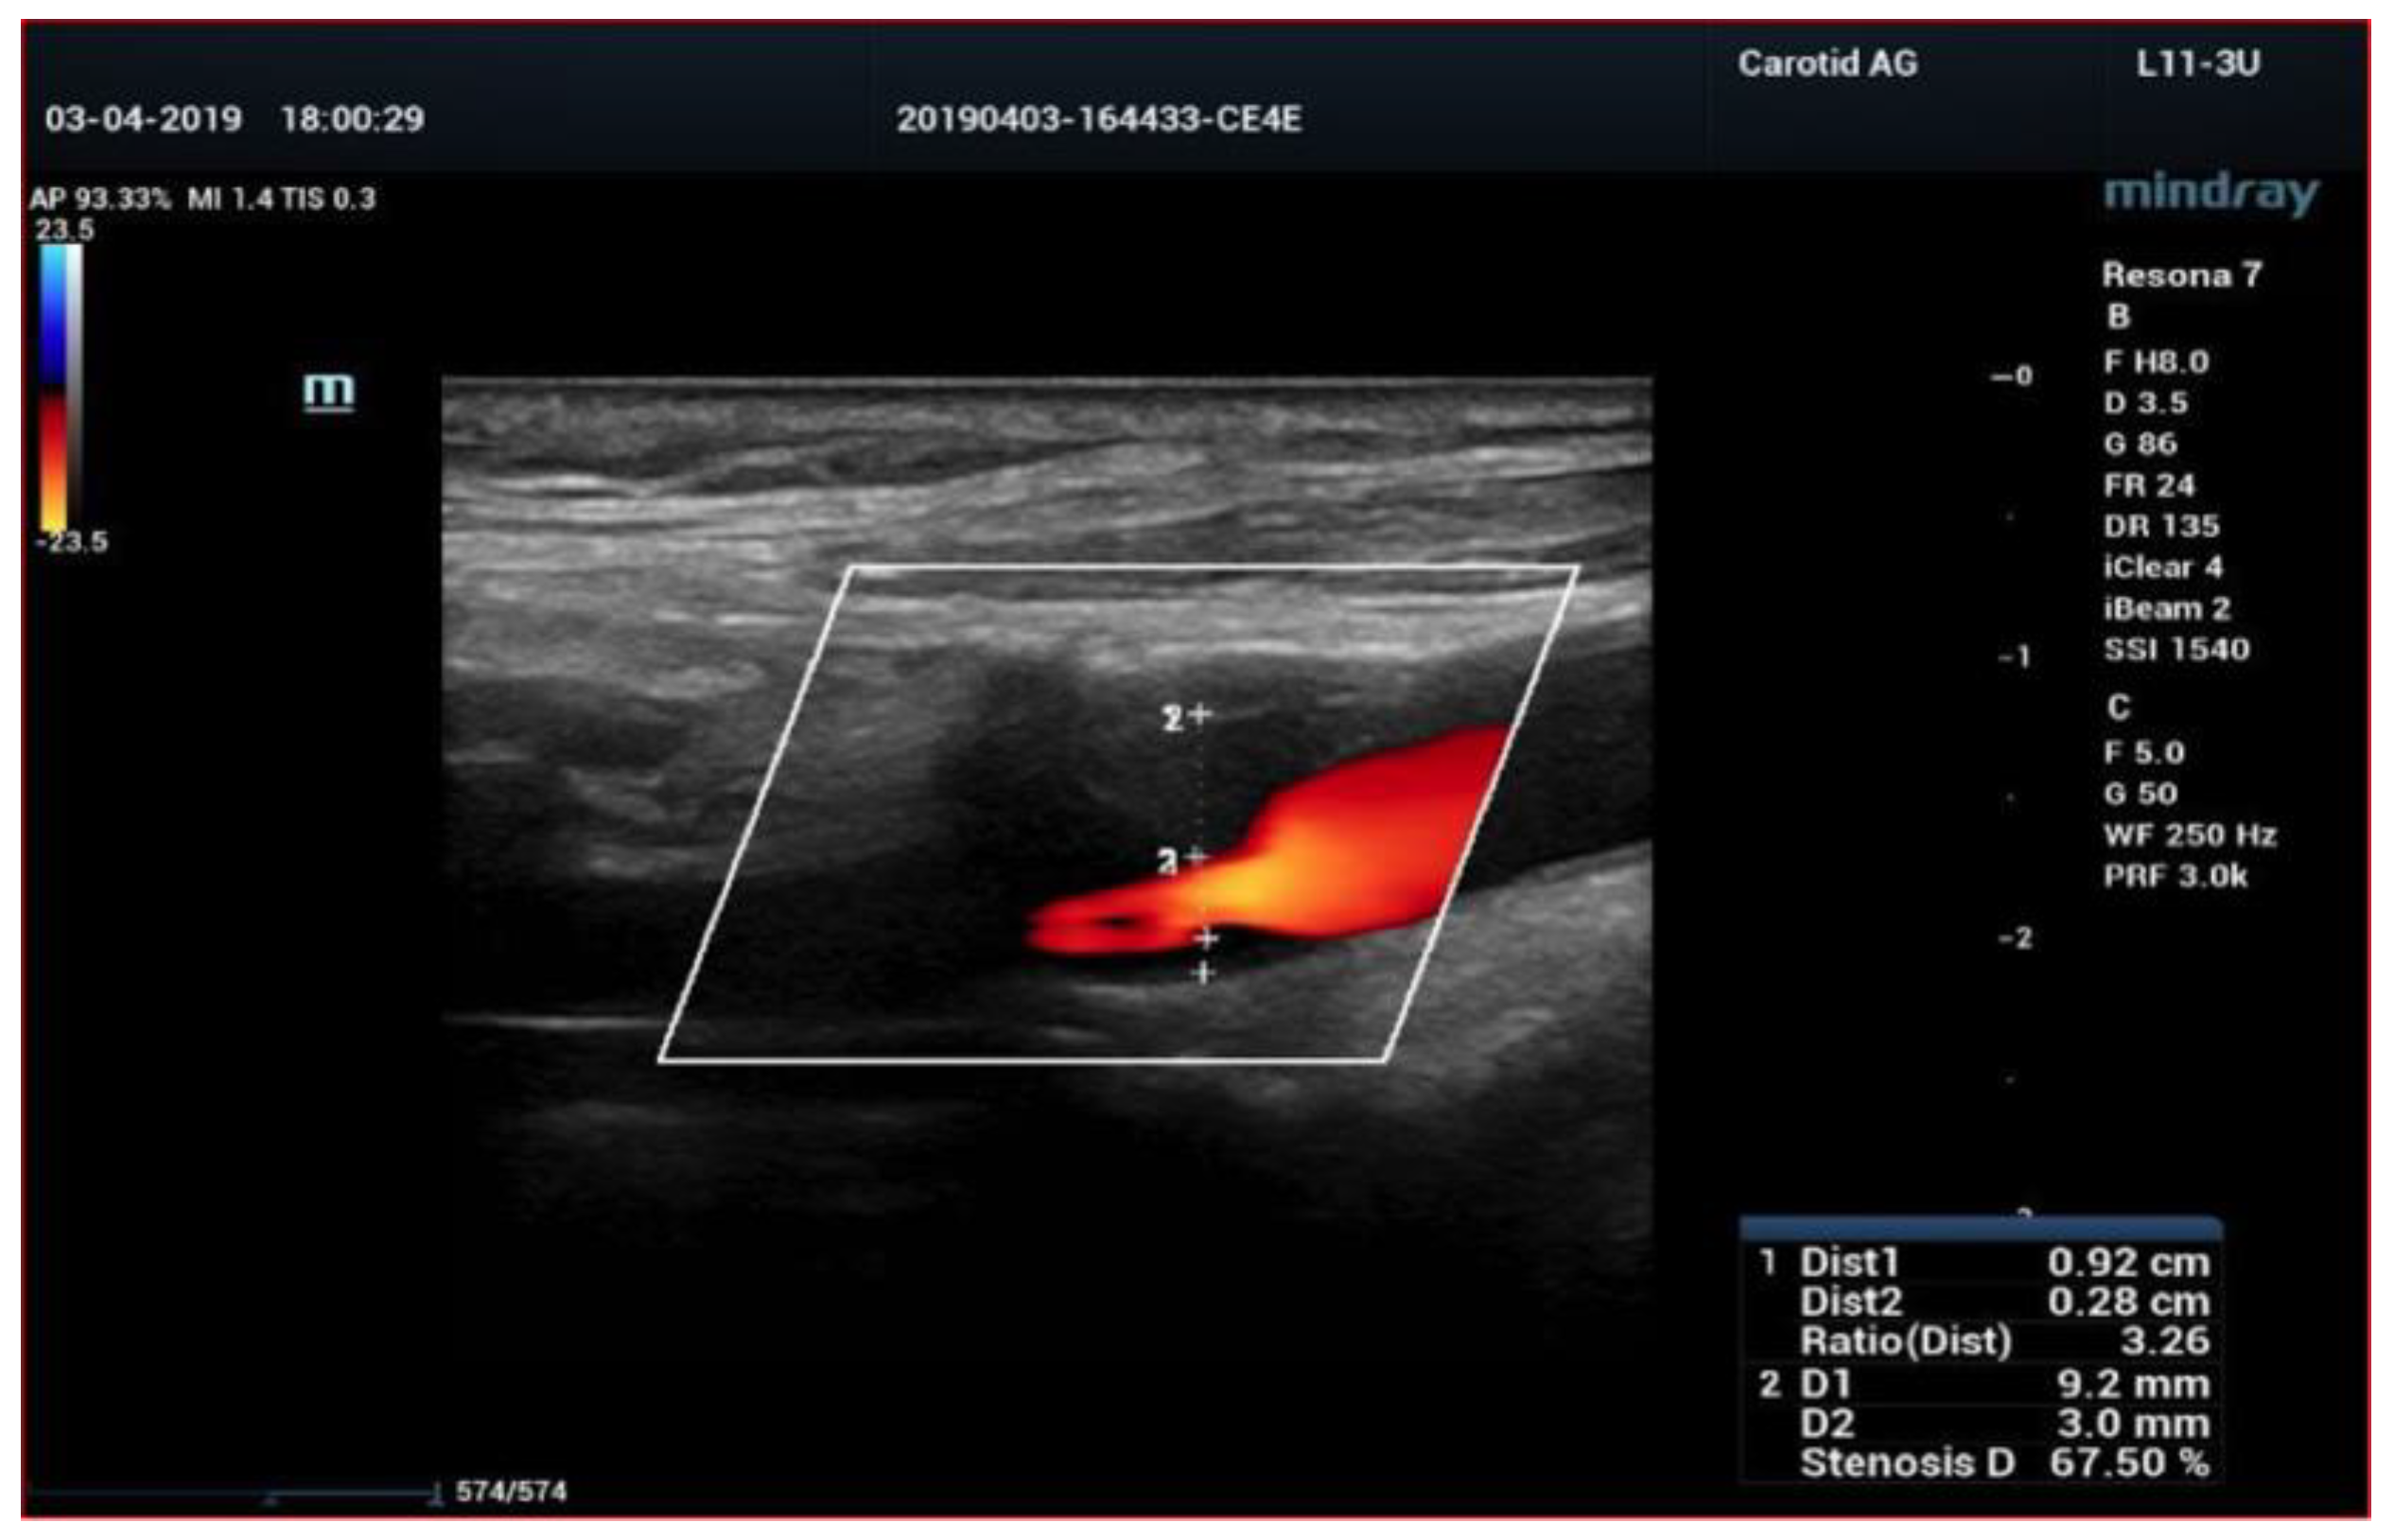

4. Color-Doppler Ultrasound (CDUS)